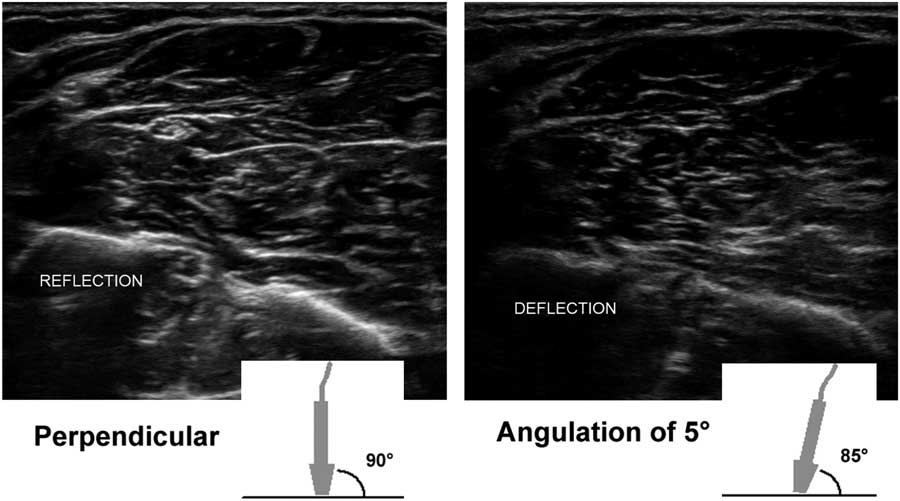

The most important aspect of transducer handling to create optimal nerve and muscle ultrasound images is choosing and maintaining a correct scan angle. It cannot be emphasized enough how crucially important it is to have a perpendicular scan angle to the tissue of interest to get a good image on screen. This is because only sound waves that are reflected back to the transducer will produce image information for the machine. Any sound waves that get deflected away from the transducer will not add to the image (Figure 5), thus leaving the image black. This means that in practice even a small scan angle difference of 5° from the perpendicular angle (i.e., 90°) already results in a visibly darker and less informative image; for quantitative measurements of echogenicity, this would be flawed. The tricky part here is that the scan angle difference can both be caused by a slight tilt in the transducer position, as held by the operator, and also by a change of direction or course of the underlying anatomical structure of interest, such as the median nerve in the proximal forearm that runs deep and medially between the two halves of the pronator teres muscle. If the transducer angle is not adjusted to match such a course, the nerve will become blacker and less clearly visible, no matter how many image-enhancing features are used. This also means that, for optimal nerve ultrasound, having a knowledge of the position and course of the nerve of interest in its anatomical context is crucial. It may be necessary to approach the nerve (and hence examine the patient) from different sides during scanning of a whole nerve along its course. For example, the fibular nerve is best imaged at the level of the kneefold with the subject prone, and its proximal part below the biceps femoris tendon running toward the fibular head can be visualized if the transducer is rocked a little more laterally. However, once the nerve circles the fibular head, it is far easier to get a good angle on it and follow it all the way to the ankle when the subject is supine. The only nerve segments that are relatively black without much fascicular architecture, regardless of the scan angle, are the extraforaminal cervical roots that form the brachial plexus. This is because the roots have a relatively lower connective tissue content (around 20%), which means they have fewer reflective structures for ultrasound. The more distal nerve segments have a higher connective tissue content (around 40%-55%), making the fascicles, perineurium and epineurium more visible.Reference Schraut, Walton and Bou Monsef 15

Figure 5 Two images of the proximal ventral forearm showing the flexor muscle overlying the radius (on the left) and ulna (right), with the median nerve in the middle left. The left image shows the result of an optimal 90° scan angle, with clear reflection of the bony edges, the fascia and outline of the nerve. The right image shows a 5° probe tilt with a resulting 85° scan angle toward the bones and fascia; the amount of ultrasound that is deflected and does not return to the probe results in a visibly darker image with suboptimal delineation of anatomical structures.